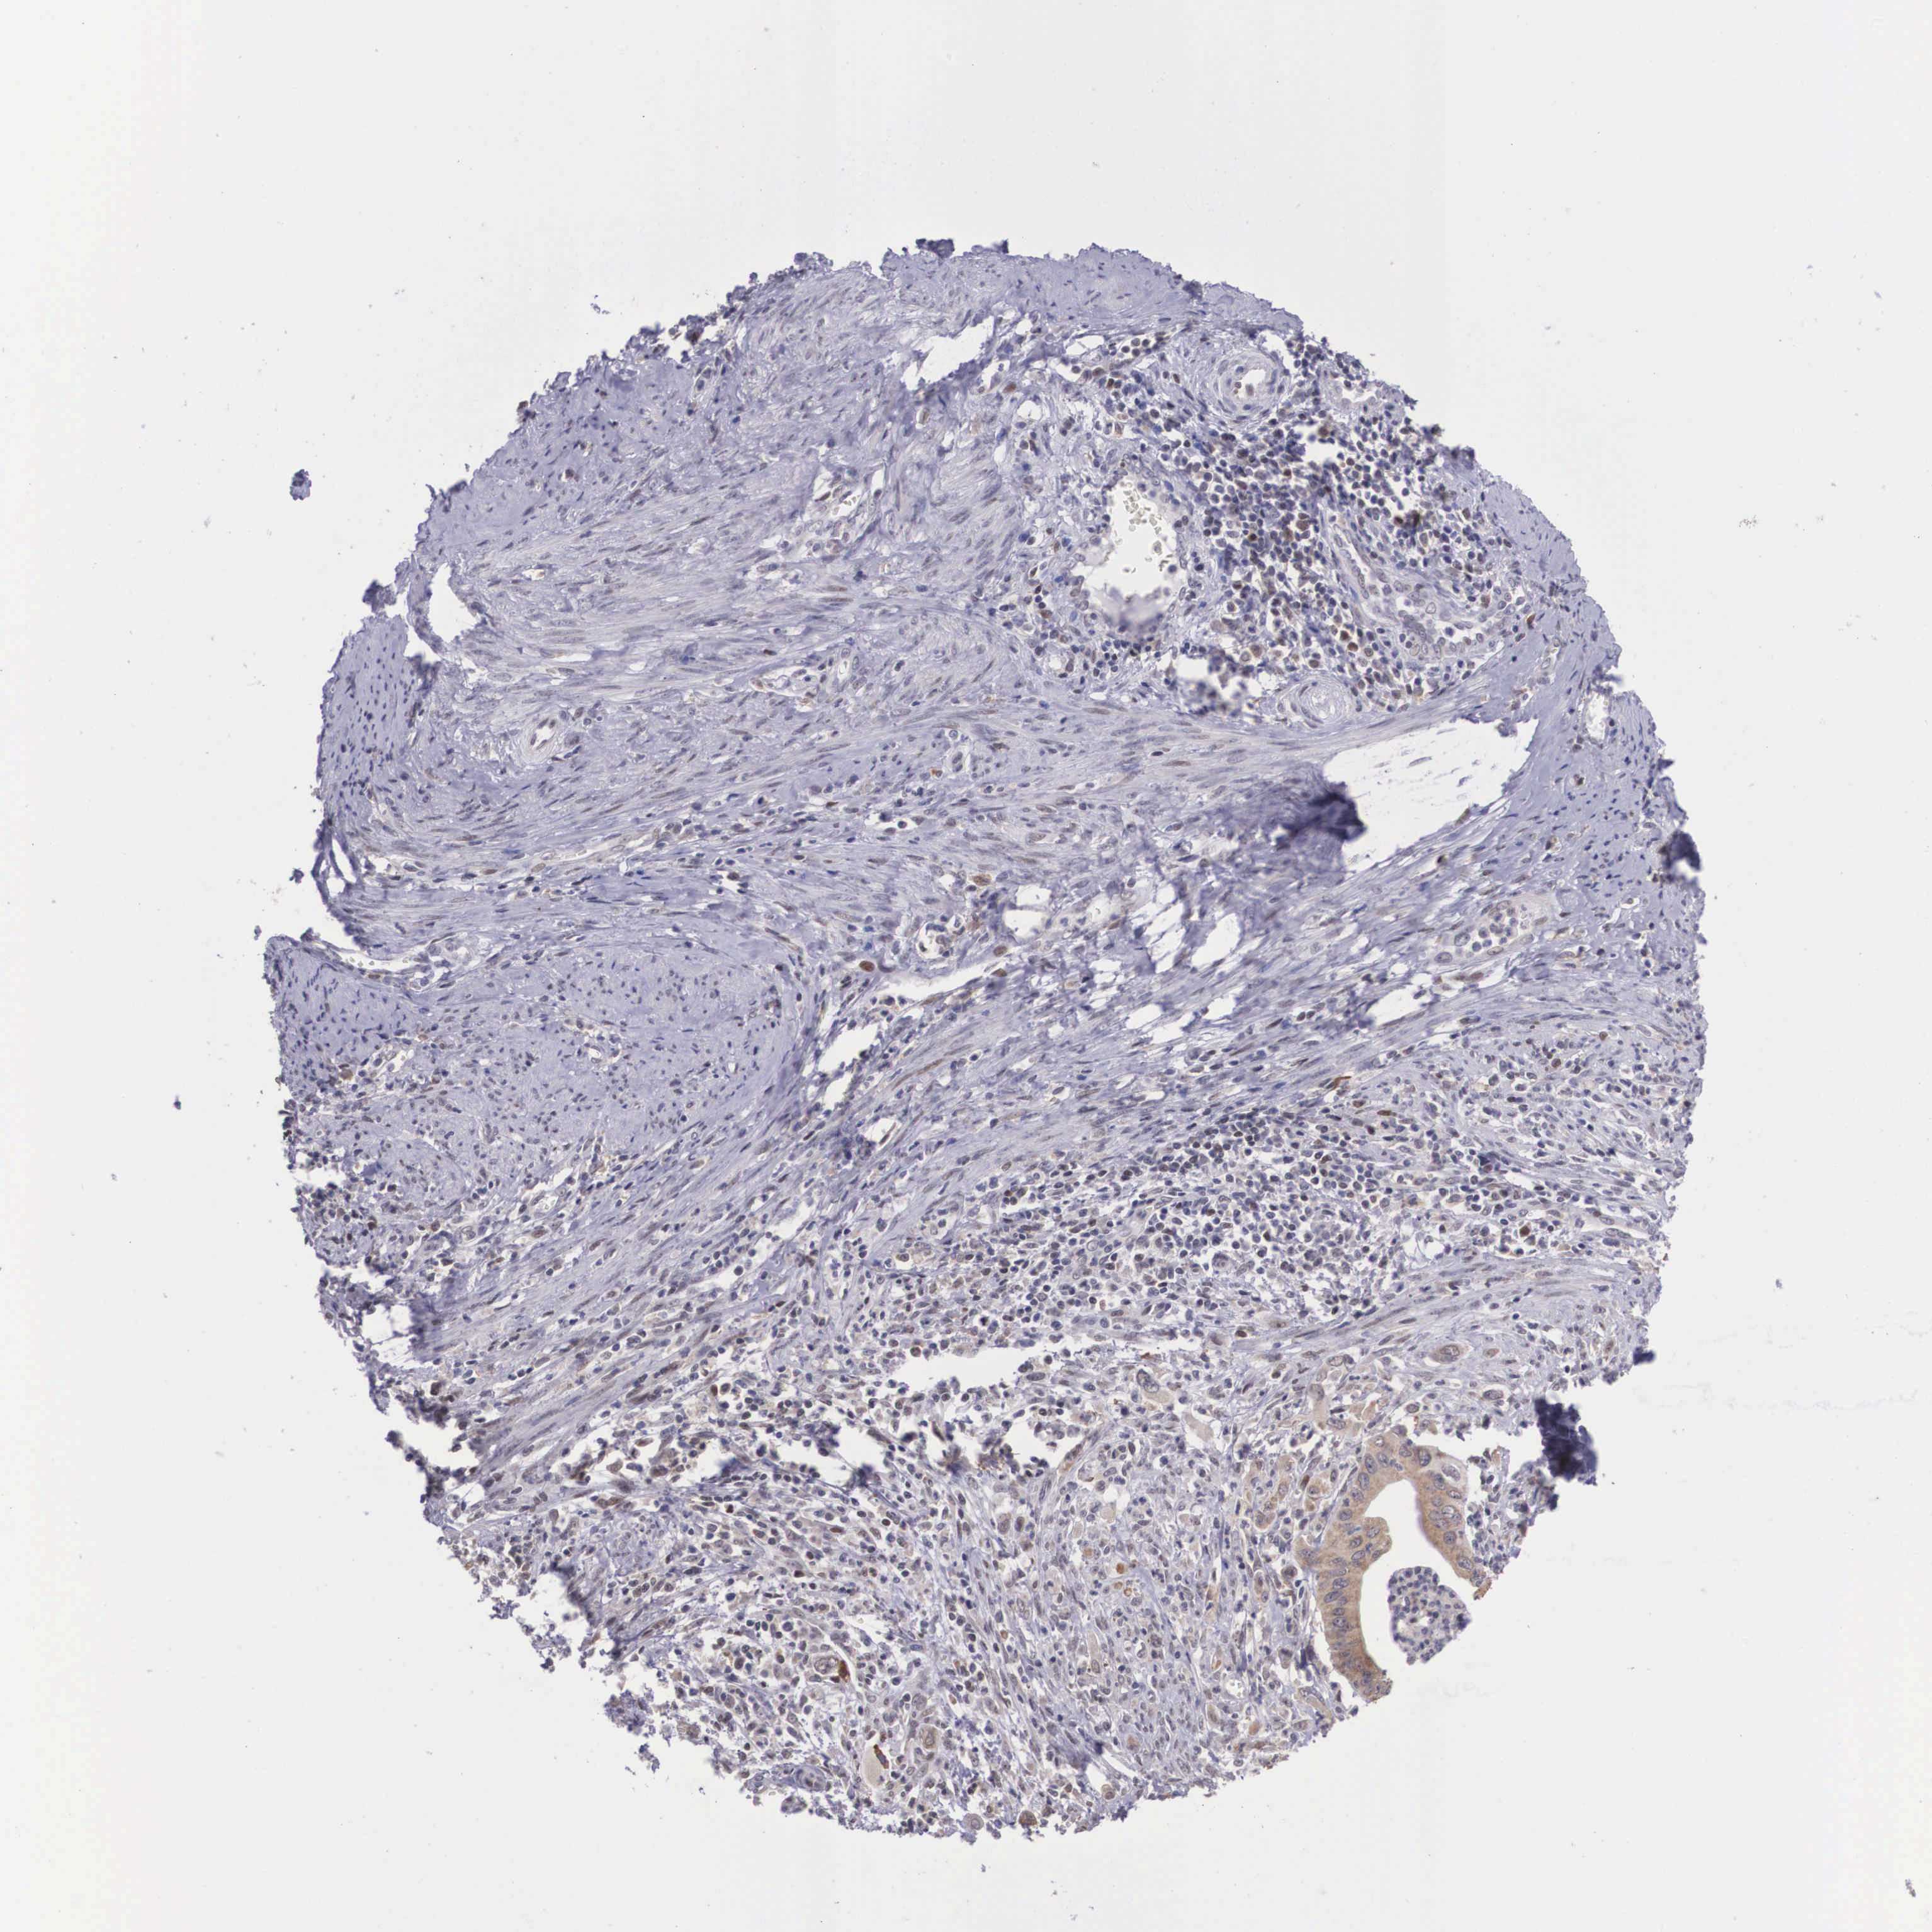

CERVICAL CANCER - Protein expressioni

A mouse-over function shows sample information and annotation data. Click on an image to view it in a full screen mode. Samples can be filtered based on level of antibody staining by selecting one or several of the following categories: high, medium, low and not detected. The assay and annotation is described here.

Note that samples used for immunohistochemistry by the Human Protein Atlas do not correspond to samples in the TCGA dataset.

Antibody stainingi

Antibody staining in the annotated cell types in the current human tissue is reported as not detected, low, medium, or high, based on conventional immunohistochemistry profiling in selected tissues. This score is based on the combination of the staining intensity and fraction of stained cells.

Each image is clickable and will lead to virtual microscopy that enables deeper exploration of all samples and also displays staining intensity scores, fraction scores and subcellular localization as well as patient and tissue information for each sample.

Antibody HPA000662

Staining

High

Medium

Low

Not detected

Intensity

Strong

Moderate

Weak

Negative

Quantity

>75%

75%-25%

<25%

None

Location

Nuclear

Cytoplasmic/membranous

Cytoplasmic/membranous,nuclear

Squamous cell carcinoma, NOS